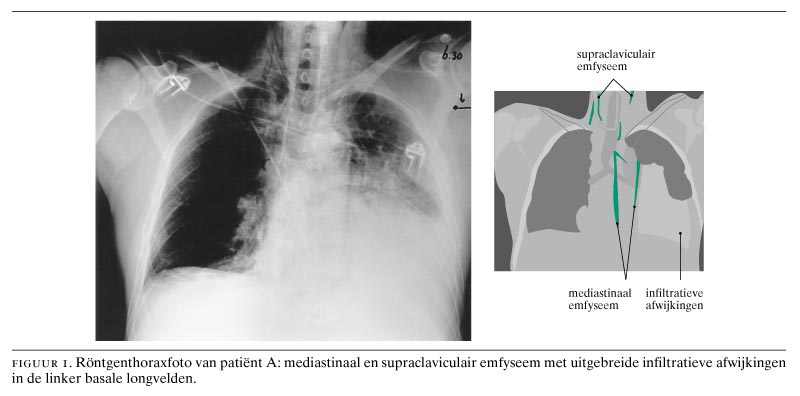

Ongeveer 4 h later werd een tweede thoraxfoto gemaakt, waarbij nu wél duidelijke afwijkingen werden gezien. Er was nu sprake van mediastinaal en supraclaviculair emfyseem en een toename van de afwijkingen in de linker basale longvelden (figuur 1).

Het herhaalde lichamelijk onderzoek bevestigde inderdaad de aanwezigheid van subcutaan emfyseem supraclaviculair. Een CT-scan van de thorax liet veel lucht zien rond de distale oesofagus en uitgebreide consolidatie in het onderveld van de linker long. Het hierna uitgevoerde röntgenonderzoek van de oesofagus met waterig contrast toonde geen afwijkingen.